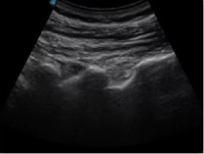

不同的探頭對應于不同的臨床領域,不同的探頭頻率也應用于不同的人體組織。超聲波在人體中的衰減與探頭頻率有關,探頭頻率越高,穿透力越弱,分辨率越高,而探頭頻率越低,穿透力越強,分辨率越低。因此在檢查淺表器官時應選用高頻探頭,而檢查深部臟器時則選用穿透性強的低頻探頭。